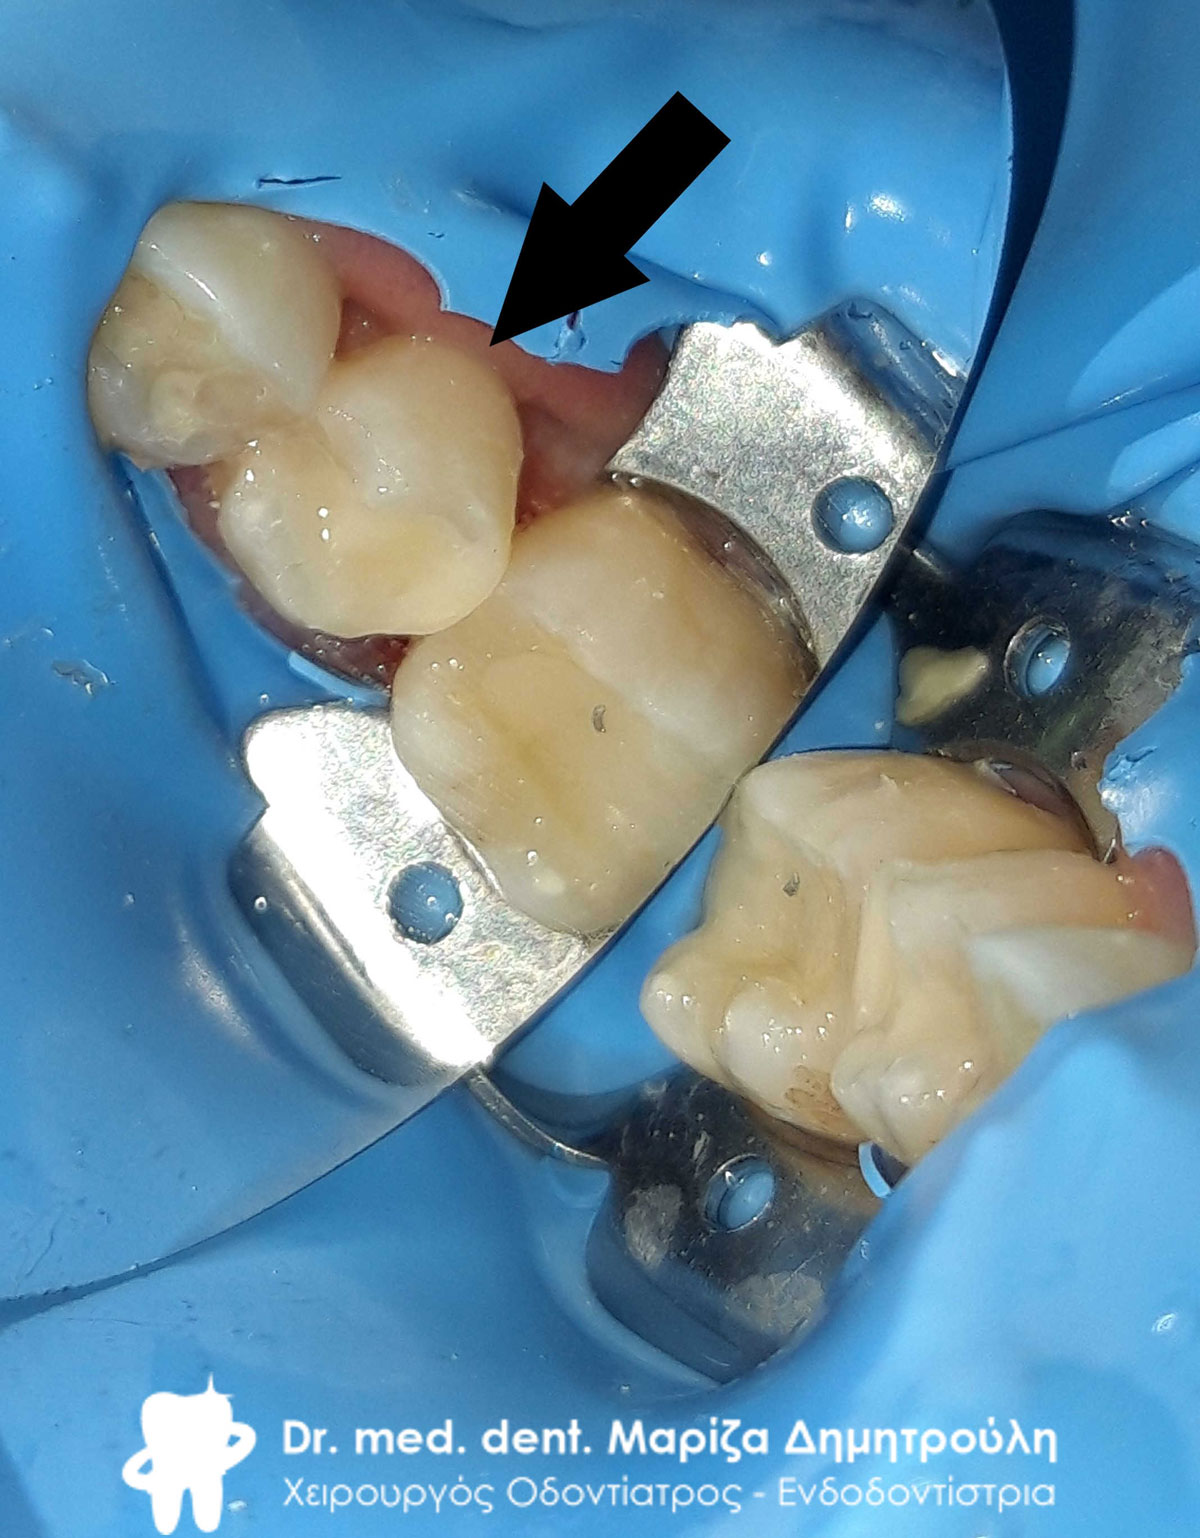

Ανασύσταση του πρώτου προγόμφιου και επανάληψη απονεύρωσης στο δεύτερο γομφίο

Ανασύσταση του πρώτου προγόμφιου και του δεύτερου γομφίου με λευκούς άξονες υαλονημάτων

Ανασύσταση του δεύτερου γομφίου και αρχική κλινική εικόνα του τρίτου γομφίου

Αφαίρεση του μεταλλικού άξονα από το δεύτερο προγόμφιο

Εικόνα της ρίζας του πρώτου προγόμφιου μετά την αφαίρεση του μεταλλικού άξονα

Αφαίρεση του διπλού μεταλλικού άξονα από τον πρώτο γομφίο